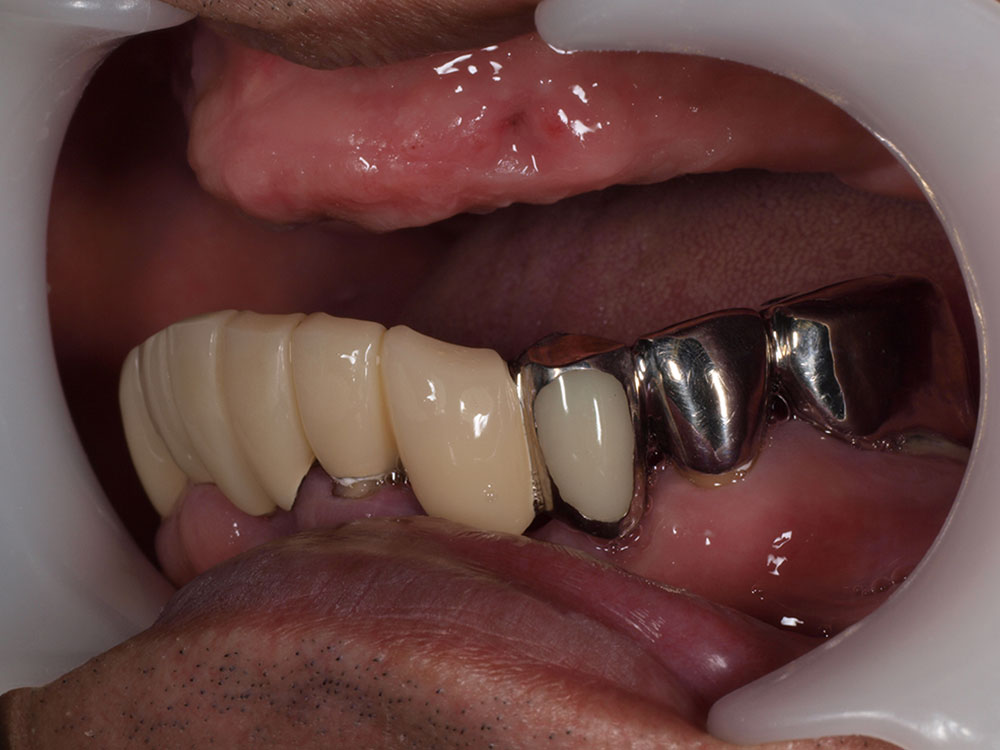

- 主訴

- 上顎入れ歯が辛い、下顎左右の歯が痛い、揺れる

- 処置内容

- 上顎6本(オールオン6) 下顎3本

- 治療費用

- 上顎:約350万円(税込)、下顎:約310万円(税込)仮歯まで5か月)

- 治療期間

- 上顎:1年(仮歯まで8か月)/約10回

下顎:8か月(仮歯まで5か月)/約7回

- リスク

- 上部構造物、仮歯の破折、術後の腫れ(3日)、人工歯根脱落リスクがあります